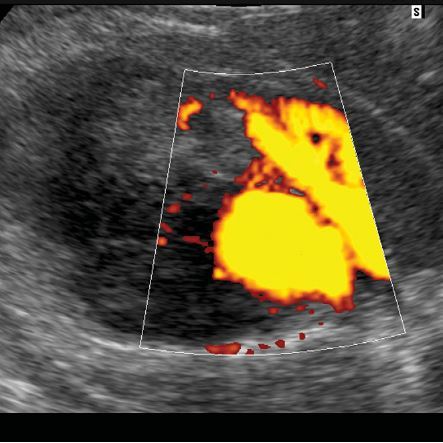

Caroli’s disease

• central dot sign = cystic lesions with central solid components containing blood flow

• complications

• biliary stones

• bild duct obstruction

• cholangitis

• liver abscess

• hepatic fibrosis –> portal hypertension

• cholangiocarcinoma

• the kidneys may also be affected with a variety of cystic diseases